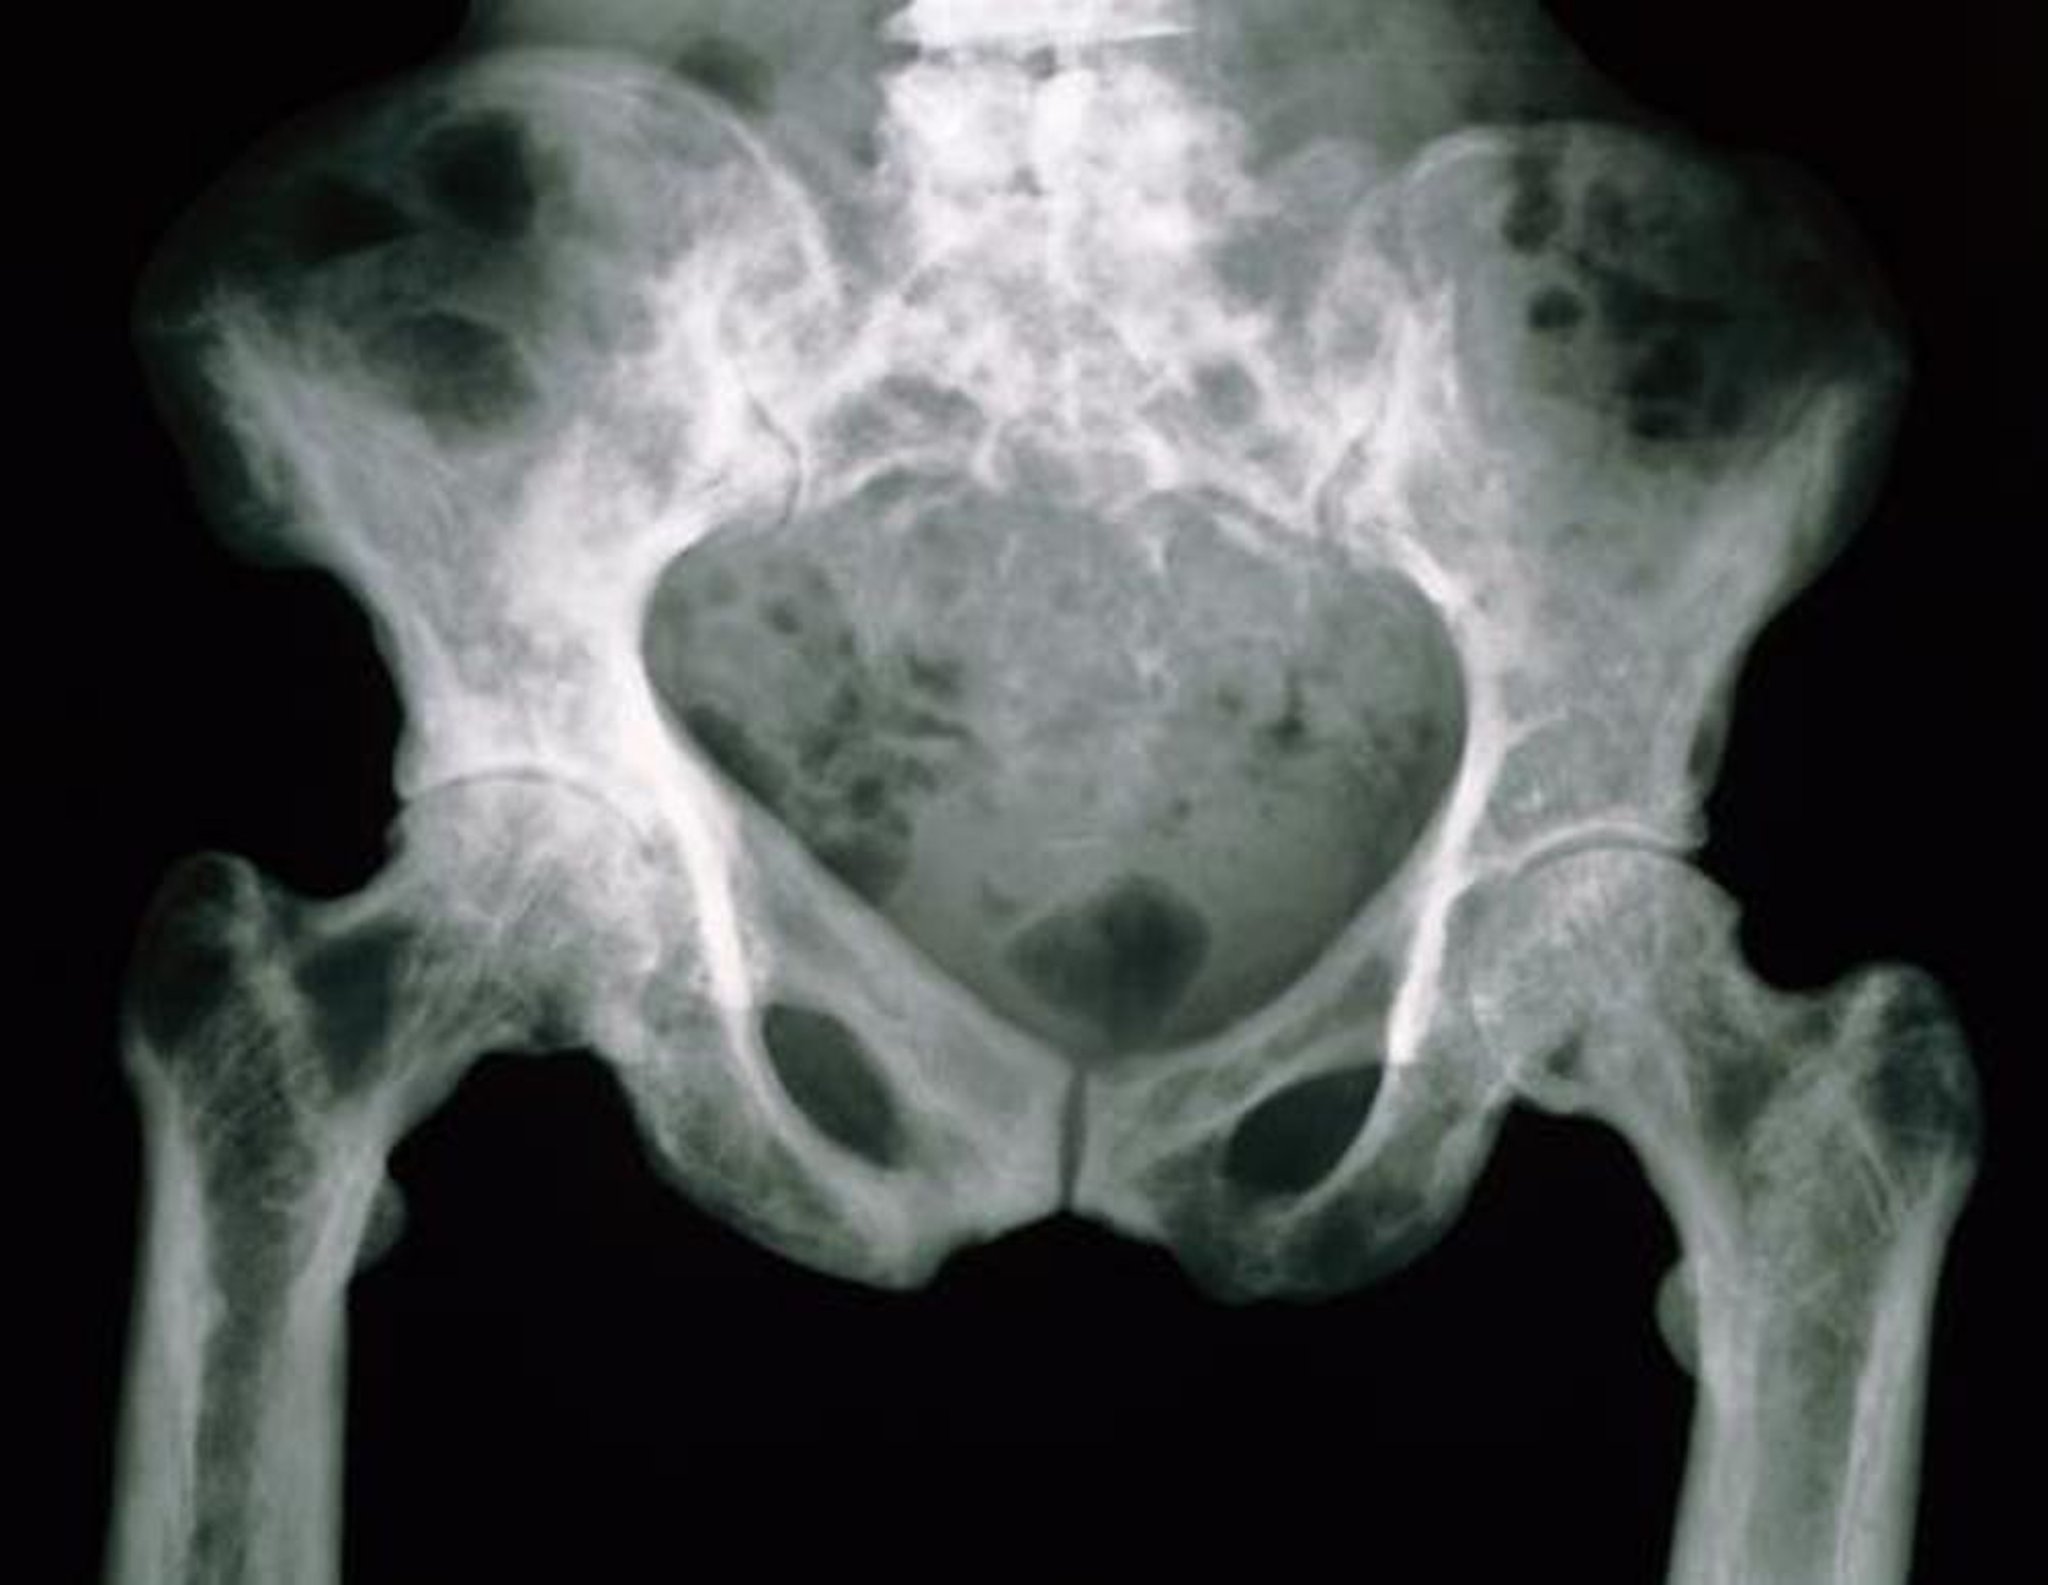

Phim chụp X-quang vùng chậu trong bệnh Paget

Xương chậu trong phim chụp X-quang này có hình dạng loang lổ do tăng mức độ xốp xương.